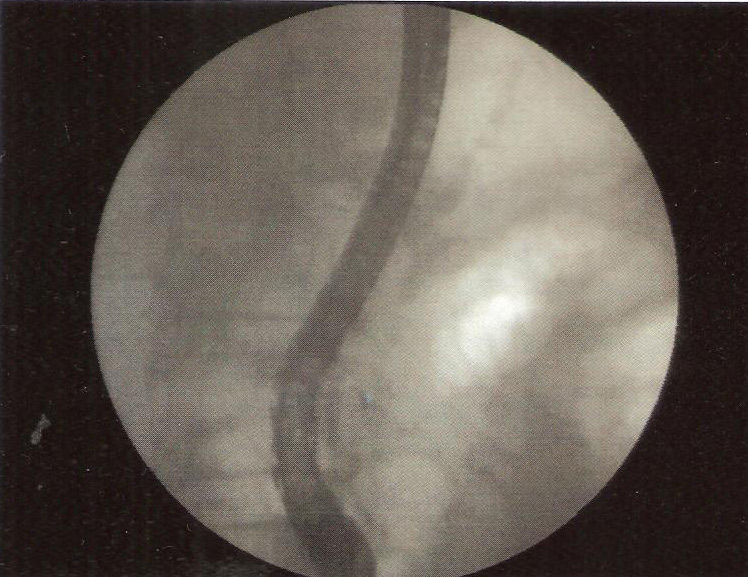

ERCP was performed.Selectuve cannulation was done of the pancreatic duct .The wire could negotiate the stricture in the neck but even a 5 Fr biliary dilator could not.A stent retriever was screwed over the wire and the stricture dilatation obtained with removal of fragments of stone.A pancreatic stent was placed .

The stent was removed after 2 months to obtain free pancreatic duct drainage.The patient was pain free.